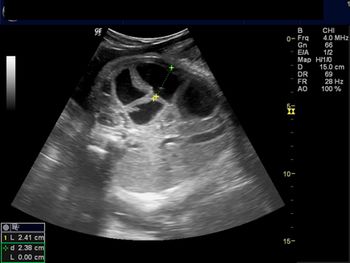

Challenge your diagnostic skills: Is this fetal heart normal or abnormal?

Challenge your diagnostic skills: What’s odd about this 16-week pregnancy?